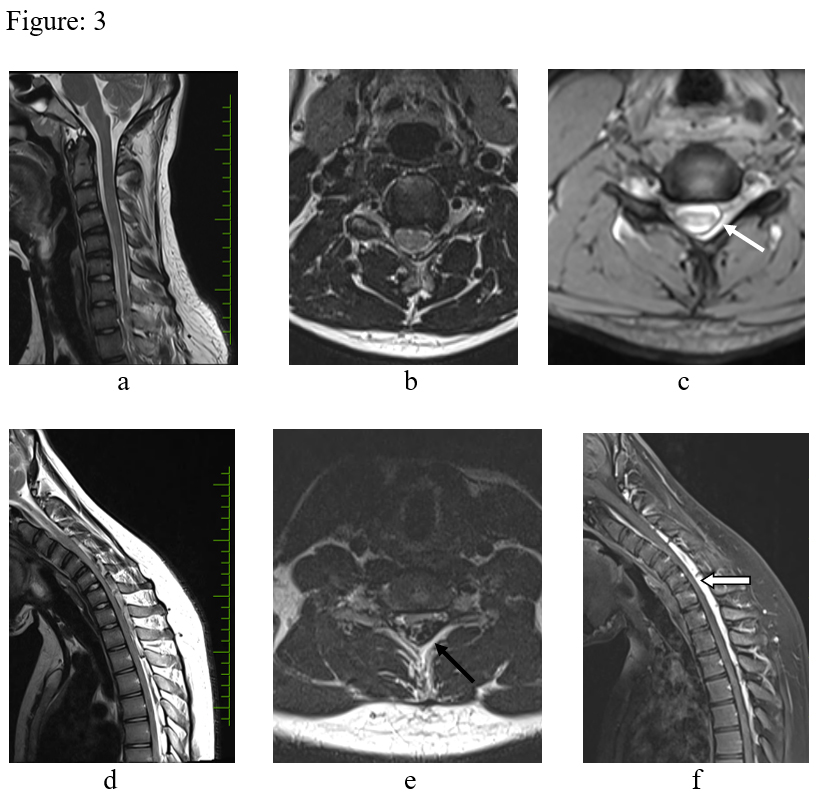

Figure: 3 – T2 sagittal (a) T2 axial (b), medic axial (c) in neutral position. There is focal cord atrophy, asymmetrical cord flattening & loss of attachment of the dura with lamina (white arrow). d, e & f – Flexion study (d, e – T2 sagittal & axial, f post contrast T2 sagittal) – There is anterior displacement of the dural sac, widened lamino-dural space with venous engorgement (black arrow) and epidural enhancing component (block arrow).